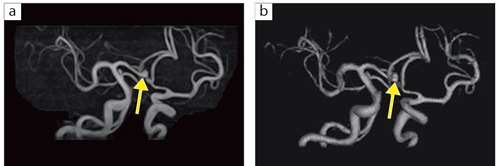

■症例2:未破裂前交通動脈瘤

67歳,男性。頭痛を主訴に来院。MRAにて径3mmの未破裂前交通動脈瘤(↑)を認める。 a:MRA,3D TOF(MIP),FOV:160mm,TR/TE:37/6.5,FA:30°,スライス厚:1.2mm b:MRA,3D TOF(VR),FOV:160mm,TR/TE:37/6.5,FA:30°,スライス厚:1.2mm